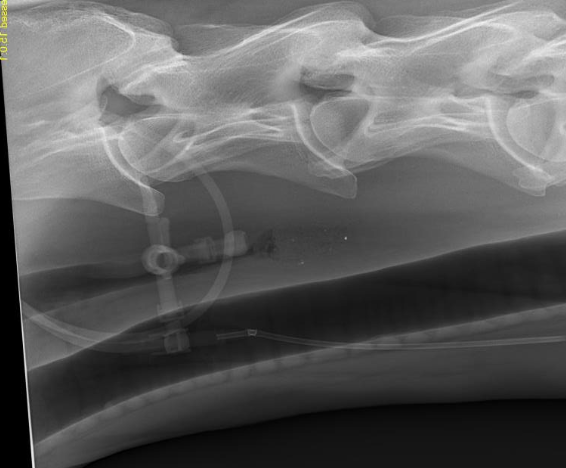

-radiographs

how are radiographs helpful for diagnosing choke in horses?

can help identify:

-location and length of obstruction

-evidence of esophageal rupture

-esophageal abnormalities (diverticulum, megaesophagus, stricture)

-assess lungs